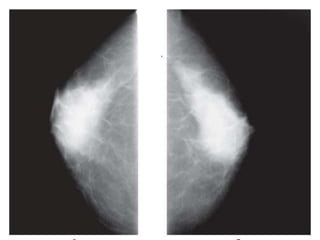

 Adipose tissue comprises a large portion of most breasts

and is radiolucent.

 The radiographically visible densities include:

(i)varying degree of ducts

(ii)lobular elements

(iii) fibrous connective tissues structures.

 The supportive connective tissue is highly cellular and

richly vascularised with significant water density-

constitutes the essence of breast opacity in

mammography.

 Sexual hormones influence the degree of hydration of the

adult breast.

 The breast is more radiolucent and better contrasted in the

first part of the menstrual cycle

 Pregnancy and lactation make the glandular and connective

tissue structures hypertrophic and more hydrated which leads

to diffuse increase in breast density.